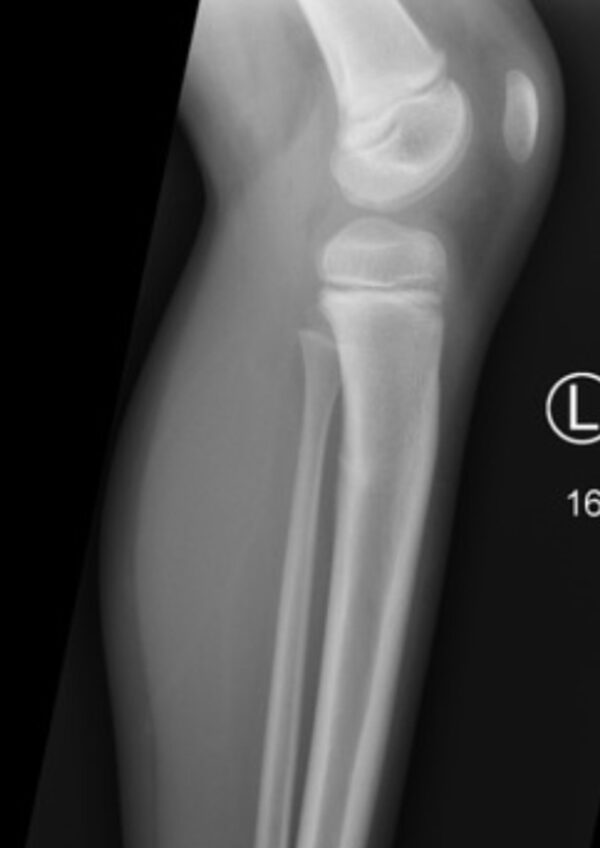

Tibial stress fractures | Radiology Case | Radiopaedia.org

X-RAY

MSK